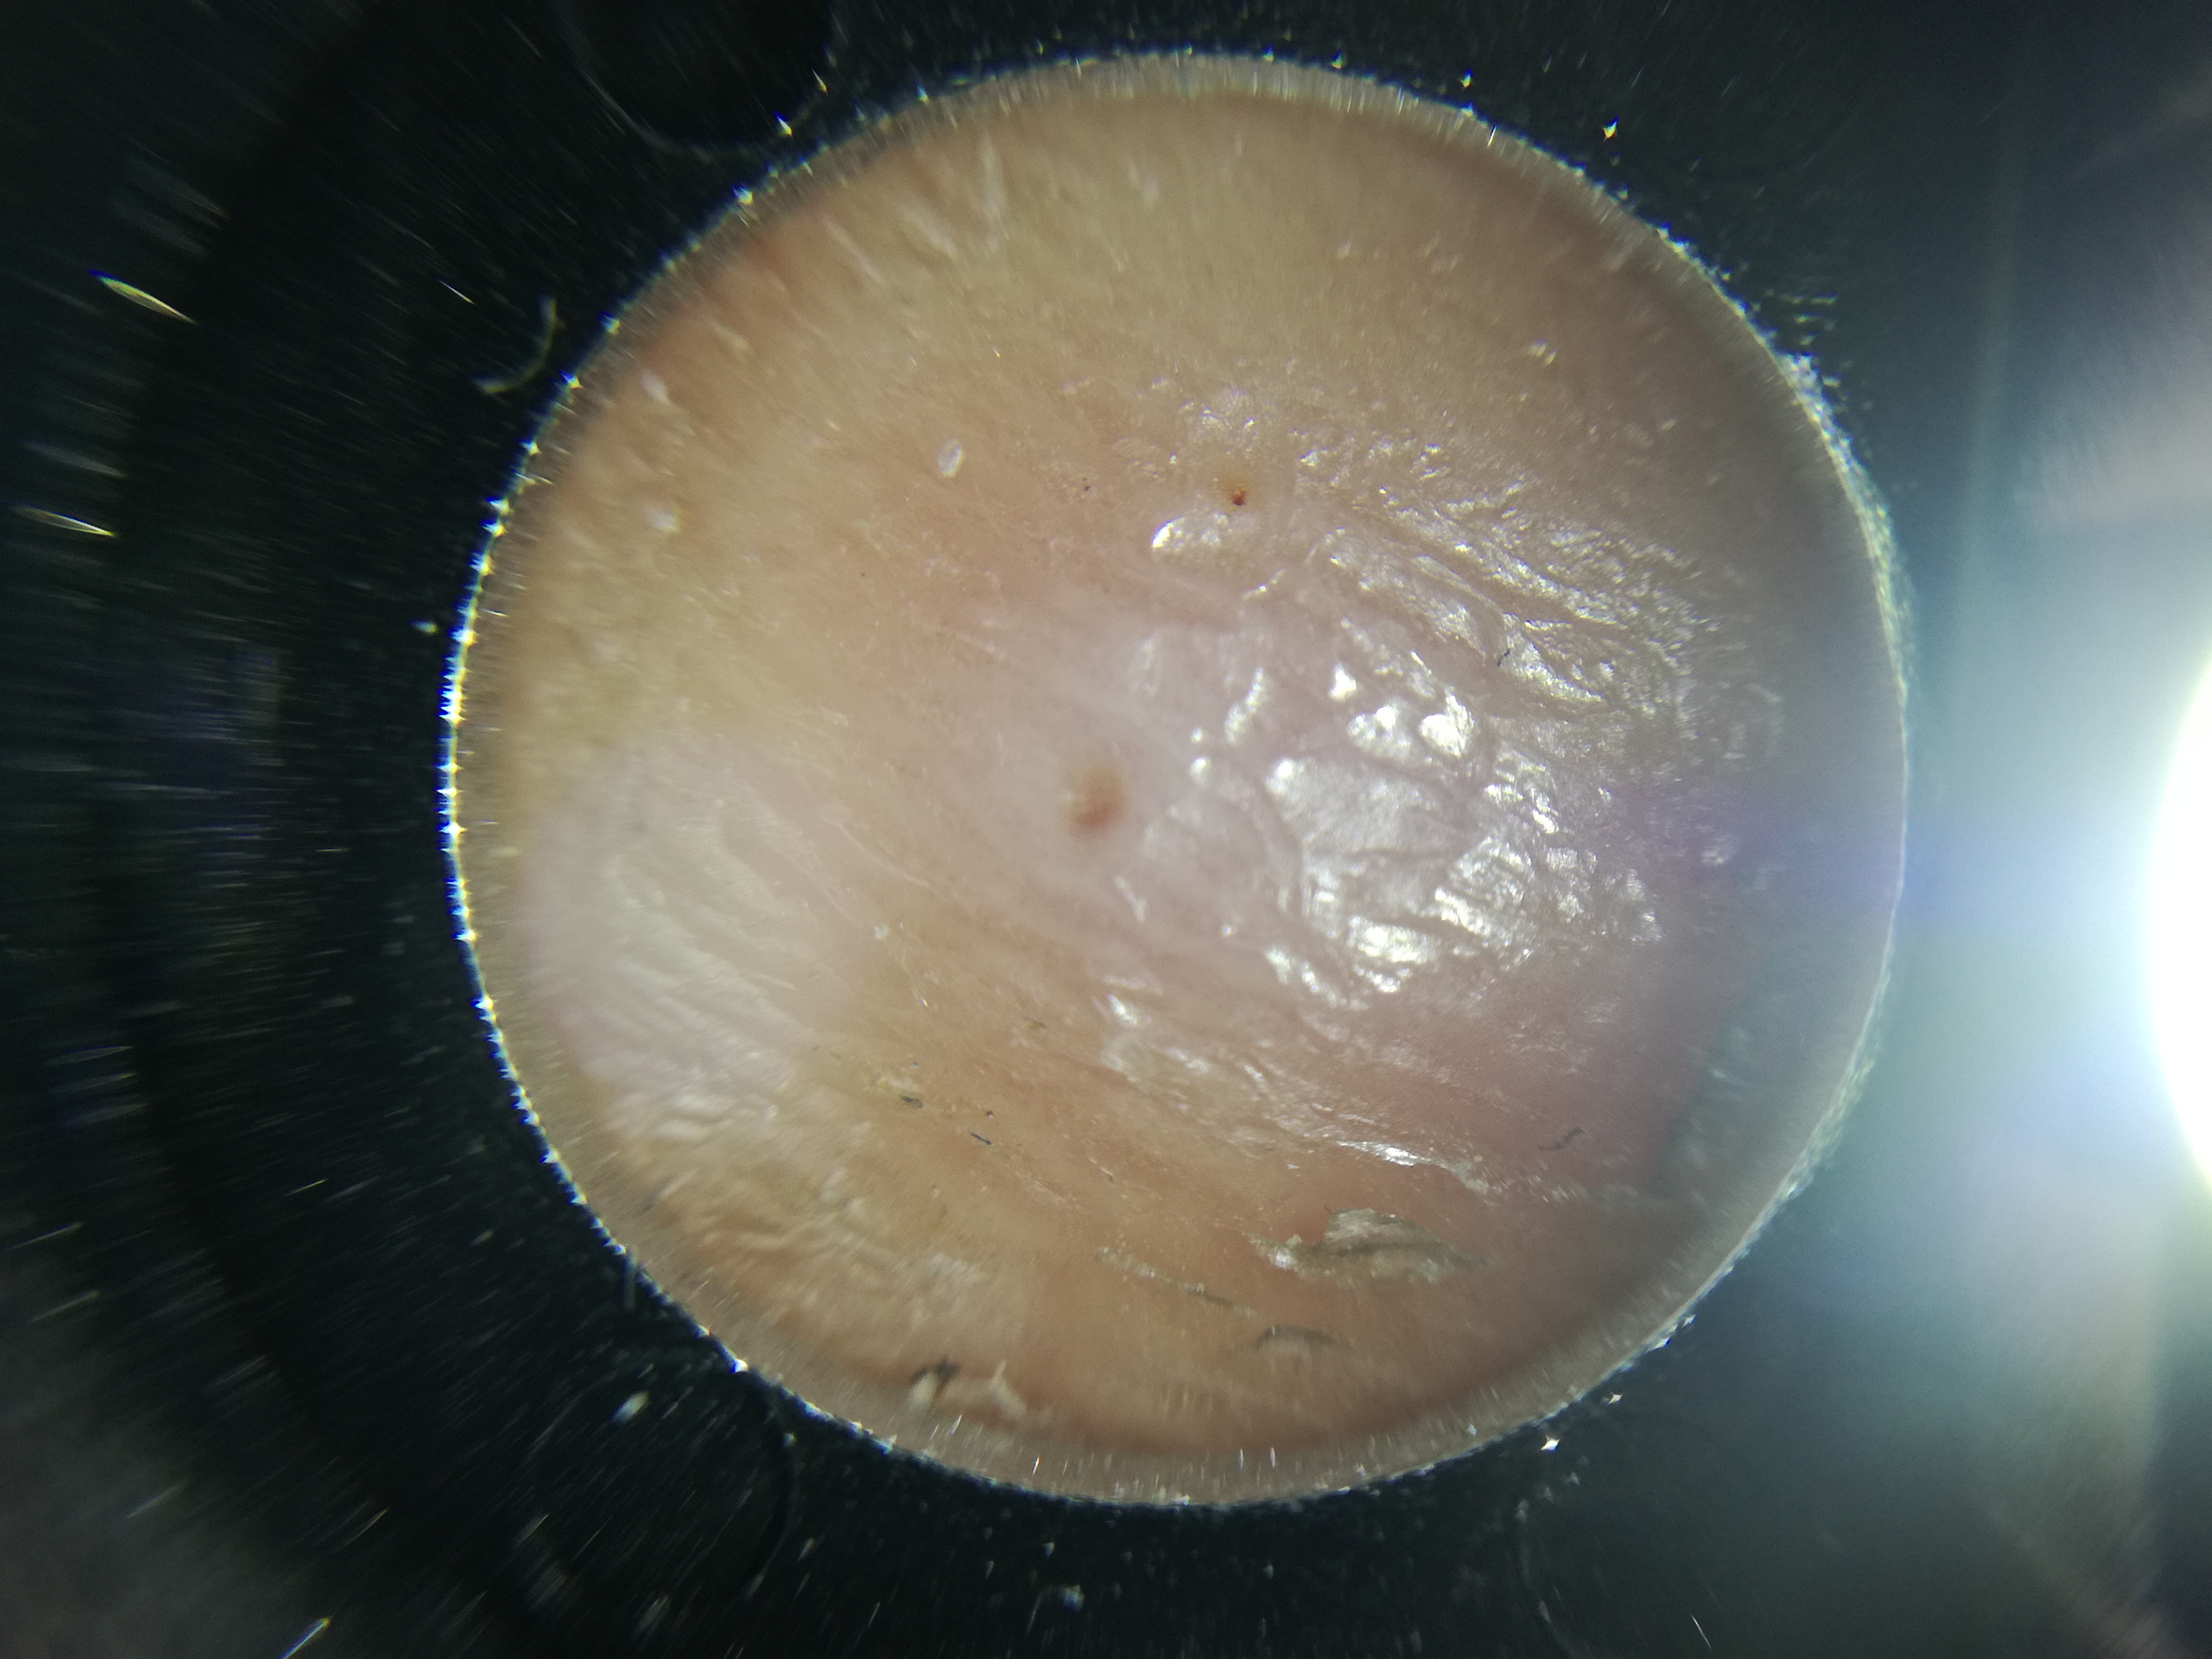

Buonasera a tutti, sono nuovo e ho bisogno del vostro aiuto. Da diverse settimane ho un puntino che sembra un inspessimento della pelle, un callo insomma, sotto il piede, che mi dà un leggero dolore quando cammino, ma che mi fa veramente male se lovado a toccare localmente. È possibile che si tratti di occhio di Pernice? In allegato due foto del puntino in questione. Rimedi? Qualcuno ha risolto? Essendo anche diabetico, inizio a farmi duemila paranoie, nonostante abbia tutti i valori sotto controllo. Help!

IMG_20180913_224558.jpg

IMG_20180913_224553.jpg

[ 2.71 MiB | Osservato 5650 volte ]